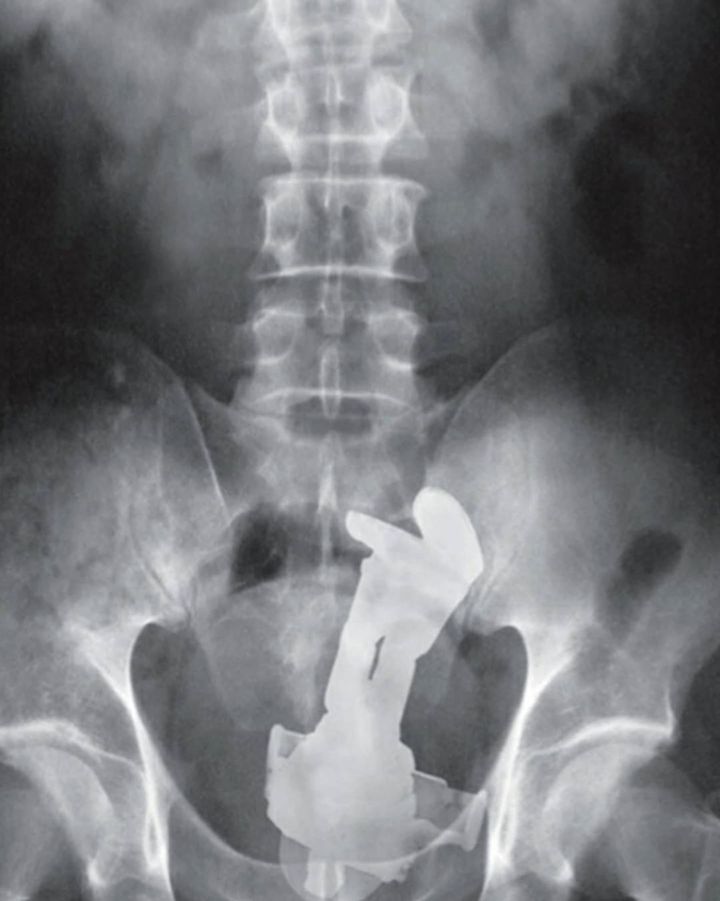

The majority of cases of rectal foreign bodies are the result of insertion during erotic activity. Typically found objects are vibrators, dildos, light bulbs, candles, shot glasses, and bottles. Some rectal foreign bodies may have been initially swallowed but later present with complications in the rectum. Patients may be very embarrassed to disclose the circumstances regarding the foreign body insertion, and there may have been multiple attempts at self-removal. Typical clinical findings of a rectal foreign body are pain with defecation, abdominal pain, rectal bleeding, pruritus, and constipation. Delays in seeking medical attention and multiple attempts at self-removal can lead to mucosal edema and muscular spasms, making removal of the object more difficult.